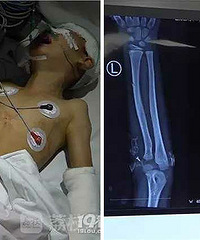

5岁女孩睡梦中 被姥爷打成粉碎性骨折

辽沈晚报11月30日报道,5岁的方方(化名),睡梦中的她被姥爷锤晕,右眉骨粉碎性骨折,头骨开裂。与方方一起受伤的还有她的妈妈,头部被父亲打伤5处。